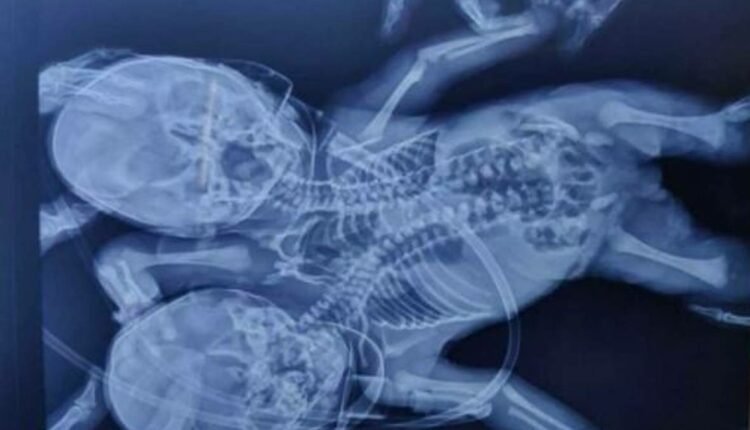

Ινδία: Γεννήθηκε μωρό με δύο κεφάλια, τρία χέρια και δύο καρδιές

Έκπληκτοι έμειναν γιατροί στην Ινδία, όπου όπου ένα μωρό γεννήθηκε με δύο κεφάλια, τρία χέρια και δύο καρδιές.

Η μητέρα, Shaheen Khan και ο σύζυγός της, Sohail, περίμεναν πλήρως σχηματισμένα δίδυμα, αλλά σοκαρίστηκαν όταν γεννήθηκε ένα δικέφαλο μωρό στις 28 Μαρτίου στο Ratlan, στην ινδική πολιτεία Madhya Pradesh, όπως αναφέρει η Daily Mail.

Σύμφωνα με τους γιατρούς, αυτή η διαταραχή είναι γνωστή ως δικέφαλος parapagus dicefalik όπου δύο μωρά ενώνονται με έναν κορμό που συχνά οδηγεί σε θνησιγένεια.

Όμως τα δίδυμα που συνδέονται από θαύμα έχουν επιζήσει μέχρι στιγμής και έχουν εισαχθεί σε νοσοκομείο στην κοντινή πόλη Indore για να παρακολουθούνται από γιατρούς, σύμφωνα με την ίδια πηγή.

«Τέτοιου είδους περιπτώσεις είναι σπάνιες και η κατάσταση των μωρών παραμένει αβέβαιη, ειδικά τις πρώτες μέρες», είπε ο Dr. Lahoti, ένας από τους γιατρούς. «Εξαιτίας αυτού, τους κρατήσαμε υπό παρακολούθηση» πρόσθεσε, συμπληρώνοντας ότι «δεν έχουμε προγραμματίσει καμία επέμβαση στον ασθενή».

Σημειώνεται ότι η πάθηση αυτή λέγεται ότι επηρεάζει μόνο μία στο ένα εκατομμύριο γεννήσεις.